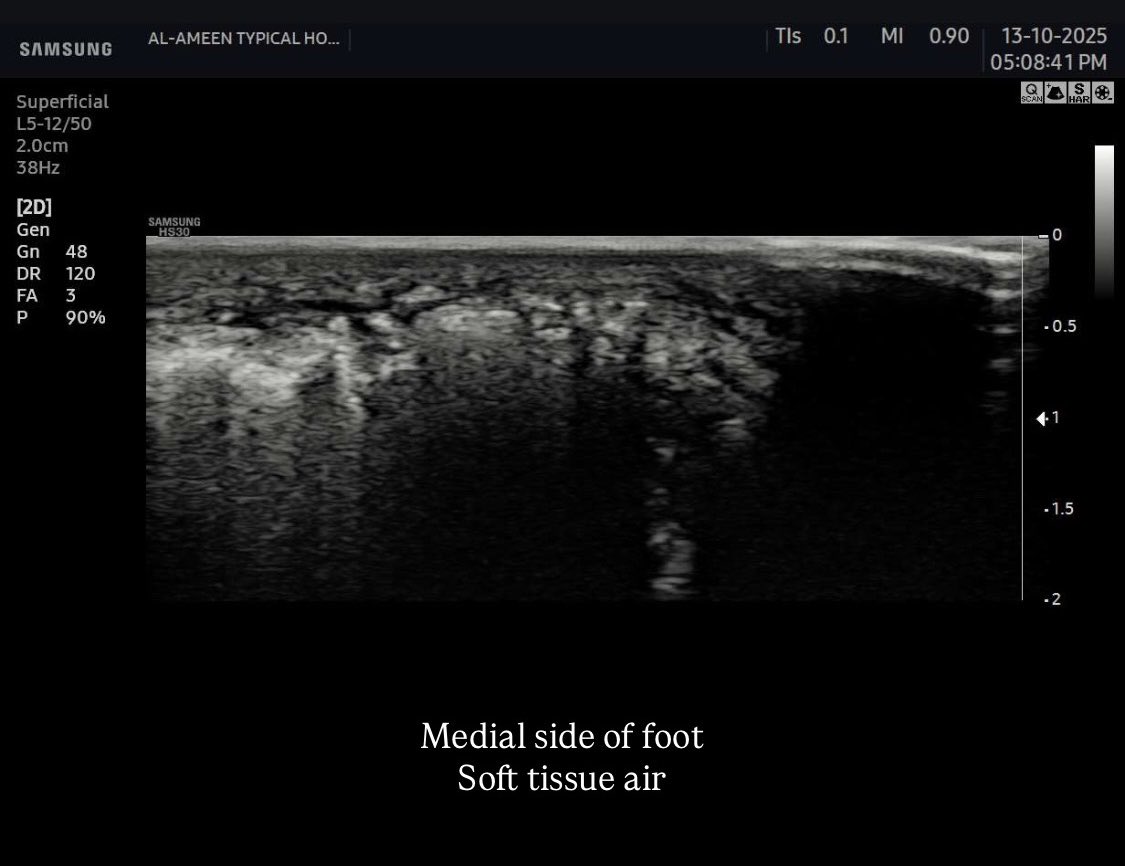

a 58 years male came with a diabetic foot And diffuse foot swelling Duplex U/S requested and done Your opinion? #EchoTech

a 58 years male came with a diabetic foot And diffuse foot swelling Duplex U/S requested and done Your opinion? #EchoTech

a 58 years male came with a diabetic foot And diffuse foot swelling Duplex U/S requested and done Your opinion? #EchoTech

a 58 years male came with a diabetic foot And diffuse foot swelling Duplex U/S requested and done Your opinion? #EchoTech

An emergent case of Popliteal artery occlusion Necrotizing fascitis (necrotizing soft tissue infection) Need urgent revascularization and debridement. #EchoTech